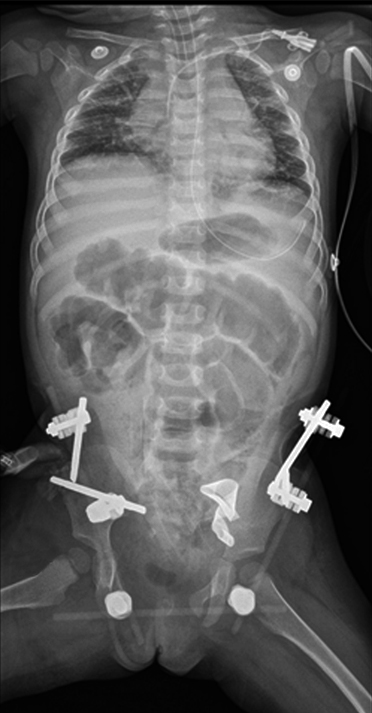

Durante la intervención se controlaron los daños mediante la fijación de tutor externo en pelvis por abordaje anterior, la colocación de 2 schanz de 4.0 en cada alerón ilíaco, y el montaje de rótulos y barras de fibra de carbón (fig. 2). El Servicio de Cirugía Pediátrica y Urología continuaron el procedimiento quirúrgico por trauma vesical y tórax cerrado. Posteriormente, se trasladó la paciente a la unidad de cuidados intensivos y se solicitó radiografía portátil de pelvis.